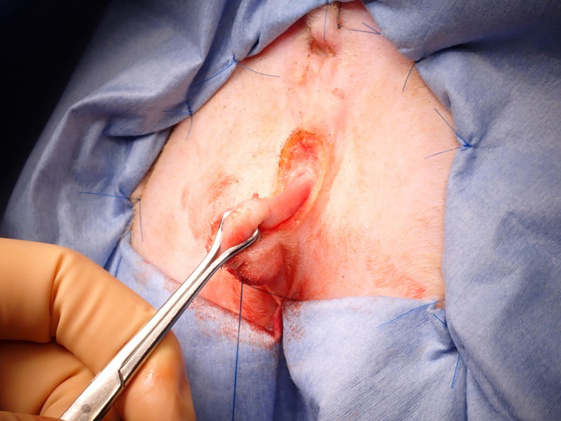

カテーテルが入ることを確認

包皮の粘膜部分を筒状に形成

術創